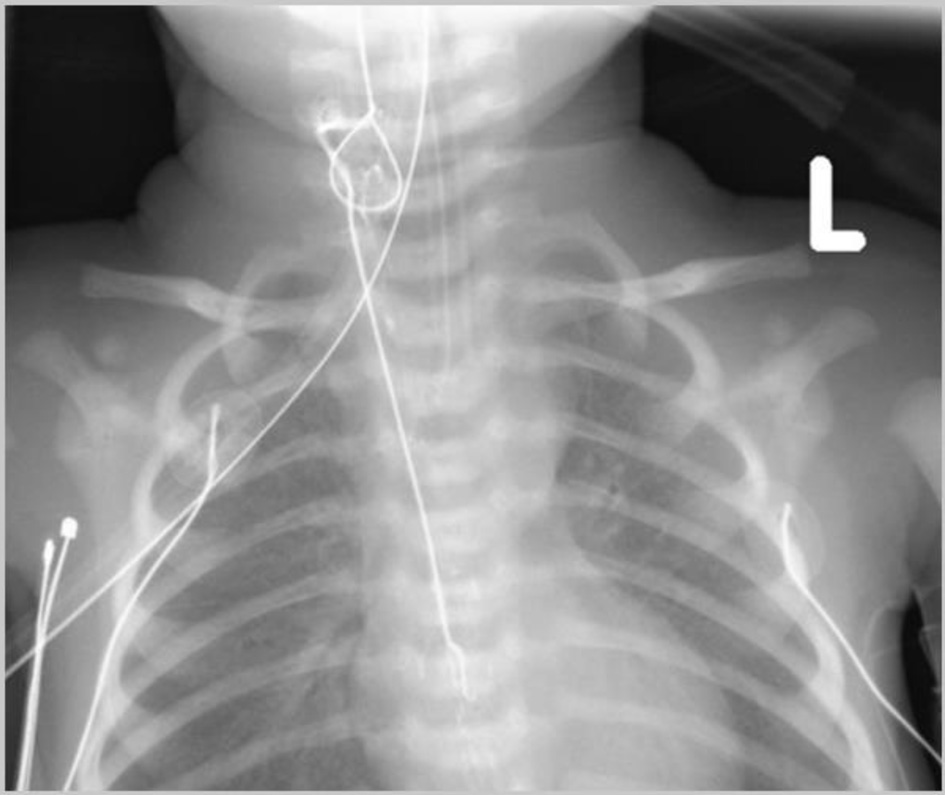

The patient was a 6-year-old, 18.2 kg, girl with history of a Wilms tumor, status post right nephrectomy (recurrence), and right paracaval mass resection who presented to the emergency department (ED) in septic shock after developing acute abdominal pain over the past 12 h. The patient had received a dose of chemotherapy the day prior to her presentation to the ED. The patient was admitted to the pediatric intensive care unit (PICU) for resuscitative measures and workup of the acute abdominal pain with a differential diagnosis including volvulus versus other etiologies of small bowel obstruction with possible ischemic bowel. The patient was subsequently taken to the operating room (OR) for an exploratory laparotomy. There was no history of prior NG use or placement. Following the induction of general anesthesia and endotracheal intubation, an NG tube was placed using standard intraoperative procedure with gentle insertion through a nare to the predetermined length. No issues were noted with placement, but during abdominal exploration its tip could not be felt within the stomach by the surgery team. An intraoperative radiograph demonstrated looping of the NG within the esophagus and its tip high in the fundus of the stomach (Fig. 1). During attempts to adjust the position of the NG tube intraoperatively, the endotracheal tube (ETT) became dislodged and there was loss of end-tidal carbon dioxide (ETCO2) waveform. The NG tube, ETT, and esophageal temperature probe were removed and the trachea was immediately reintubated without difficulty with a new ETT. Upon further evaluation of the ETT and NG, it was noted that the NG was knotted around the ETT and the temperature probe (Fig. 2), so that manipulation of the NG tube (withdrawal) resulted in inadvertent tracheal extubation. Following reintubation of the trachea, the patient tolerated the remainder of the procedure well and upon completion of the procedure was returned to the PICU.

Click for large image

Figure 1. Initial intraoperative chest radiograph revealing looping of the nasogastric (NG) tube within the esophagus and its tip in the fundus of the stomach.